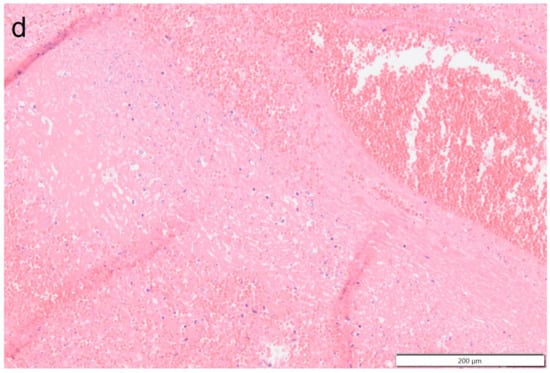

Histologically the right ventricular thrombus was characterized by a massive central zone of amorphous eosinophilic material with occasional scattered cellular debris (fibrin and necrosis) and scattered deposits of hemosiderin and hematoidin pigments. Peripherally, the thrombus consisted of a variably thick layer of connective tissue that was infiltrated by moderate numbers of macrophages, lymphocytes and plasma cells. This inflammatory infiltrate extended into the adjacent myocardium. At the site of electrode insertion, the myocardium was focally replaced by connective tissue and adipose tissue. Multiple coronary vessels had thickened walls that partially occluded the lumens. Multiple pulmonary vessels were obstructed by similar material as described in the right ventricle (thromboemboli) and here this was interspersed with small irregular vascular channels (recanalization) (Figure 9, Figure 10, Figure 11 and Figure 12). Histopathological analysis confirmed marked chronic mural endocarditis and myocarditis with chronic thrombus formation in the right ventricle and pulmonary arteries.

Figure 9.

Photomicrograph overview of the attachment site of the chronic thrombus to the endocardium of the right ventricle. Hematoxylin & Eosin staining, 2× magnification. The insets are shown and described in larger magnification in Figure 10.

Figure 10.

Photomicrographs show the attachment site of the chronic thrombus to the endocardium of the right ventricle. Hematoxylin & Eosin staining, 10× magnification. Marked mononuclear inflammation expands the myocardium (a) and (sub)endocardium at the site of thrombus attachment (b), which is further expanded by vascularized connective tissue confluent with the periphery of the thrombus (organization, (c)). The majority of the thrombus consists of a fibrino-necrotic core with islands of erythrocytes (d).